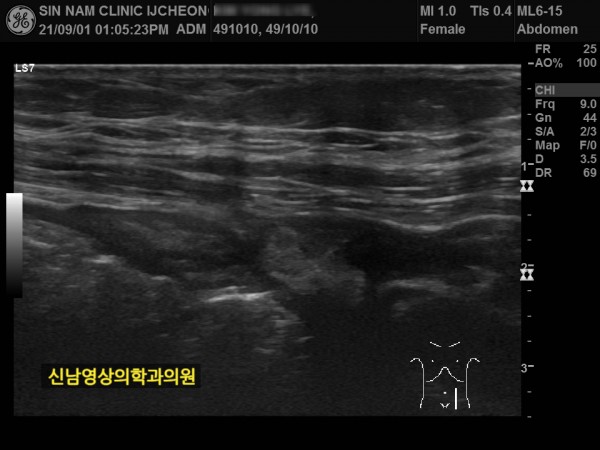

본 환자분께서는 사흘 정도 지속되는 복통과 고열로 내원하신 60대 중반의 환자분입니다.

복통 부위의 병변을 확인하기 위해서 복부 촬영과 복부 초음파검사를 진행했고, 맹장은 이상이 없고, 대장 주위로 복강삼출액(물)이 둘러싸고 있으면서 상행대장부위의 부종이 심하게 발견되었습니다.

1년 뒤 수술 부위에 탈장이 발생하셔서 탈장 수술을 받으셨던 분입니다.